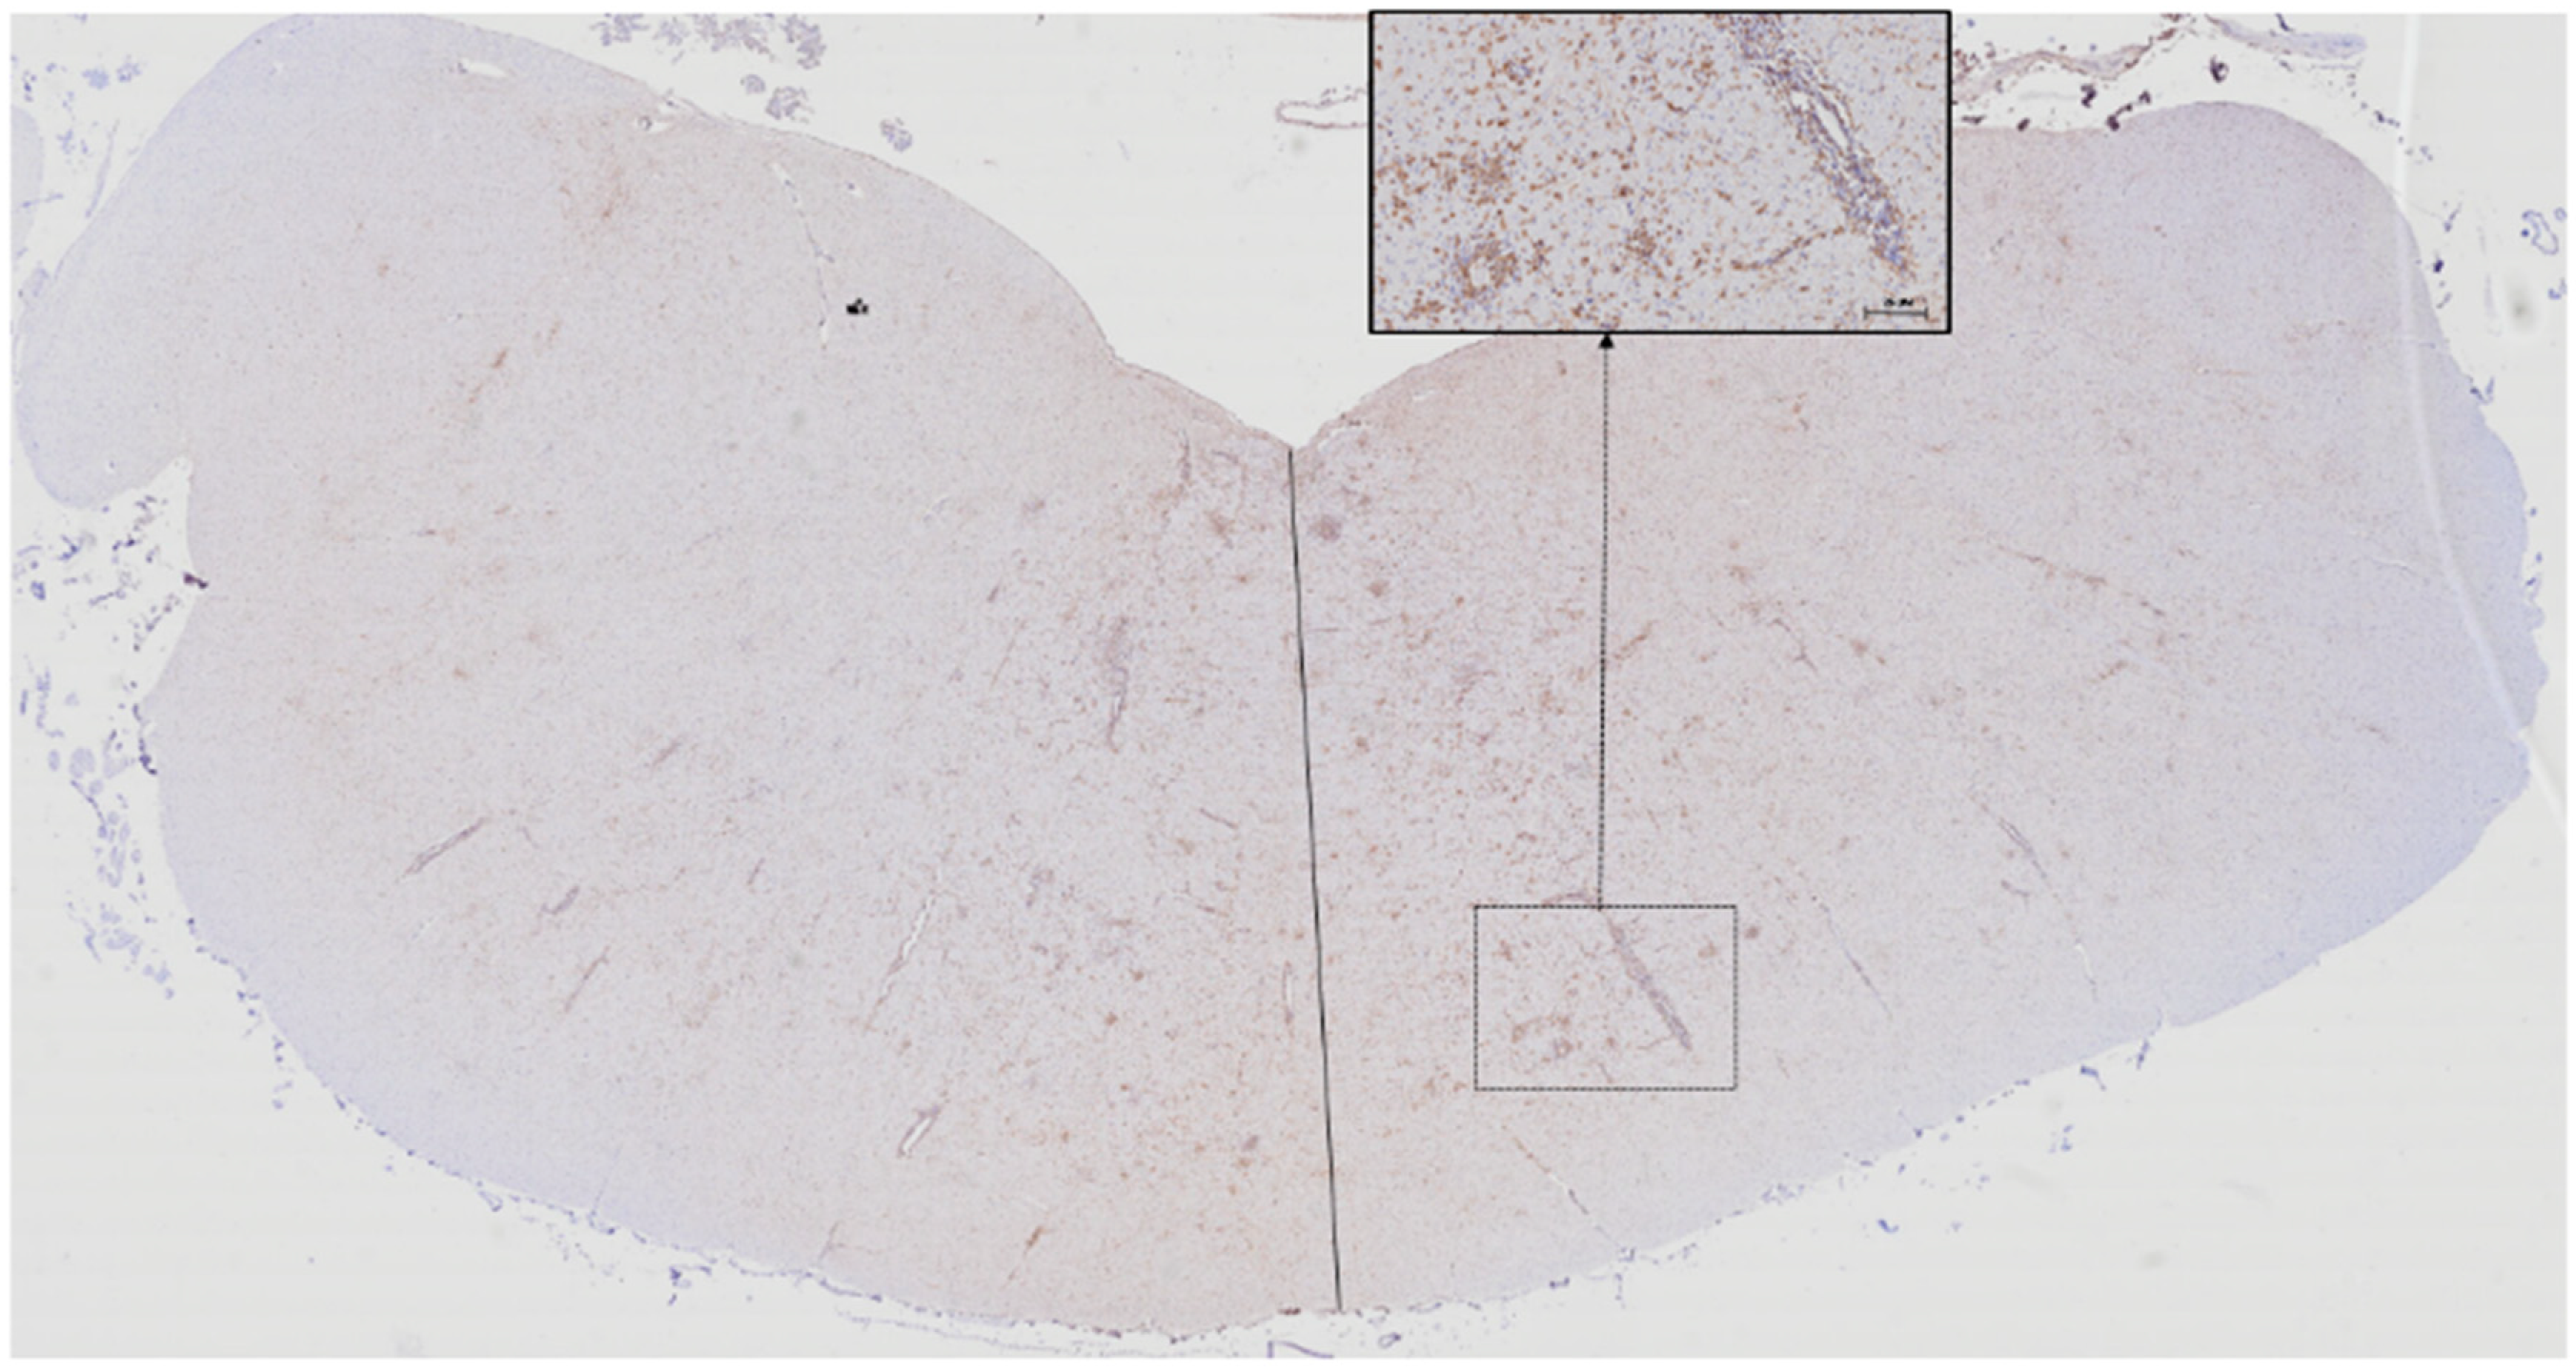

3.1. Microglia

3.2. T lymphocytes

3.3. B lymphocytes

3.4. Proportions of Microglia, T lymphocyte,s and B Lymphocytes According to Lesion Location and Severity

3.5. Astrocytes